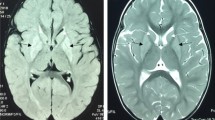

There is some evidence of genotype-phenotype correlation with higher ECHS1 activity associated with increased lifespan (Haack et al. 2015). Intermediate ECHS1 deficiency patients typically presented with developmental delay, hearing and/or vision loss, and bilateral T2 signals in the globi pallidi on brain MRI (Table 1). Age at diagnosis in these patients ranged from age 8 to 31 years.

This 8-year-old boy is a twin of Afro-Caucasian ancestry who was conceived by in vitro fertilization. The fraternal twin sister is unaffected. At 1 year of age, the child was noted to be delayed in development and to be clumsy. An MRI of his spine and brain indicated the presence of syringohydromyelia and bilateral lesions of the globi pallidi (more advanced on the left side). These lesions had low N-acetylaspartate suggesting neuronal/myelin loss. At 22 months of age, the patient experienced regression of language skills and new-onset, right-sided weakness with a febrile illness. A repeat brain MRI confirmed alterations in the basal ganglia, and MRS identified a prominent lactate peak in the left globus pallidus. He also has hematuria (due to a known diagnosis of Alport syndrome), with normal kidneys on ultrasound. With time, the child learned to walk using a walker and at 8 years of age has short sentences. He has significant truncal hypotonia, ataxia of the lower limbs, right hemiplegia, hearing loss (requiring bilateral hearing aids), and global developmental delays. The child is fed via a G-tube and has normal growth. Repeated brain MRIs indicate gliosis of bilateral globi pallidi, right caudate head, and left cerebral peduncle with no new brain lesions. Despite extensive biochemical studies, the only notable finding was a persistent, mild elevation of CSF alanine.